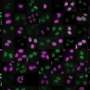

Chimeric antigen receptor (CAR) T-cell therapy is one of oncology’s most powerful ideas: Harvest a cancer patient’s own immune cells, genetically engineer them to recognize tumor cells, multiply them in a laboratory and reinject them […]